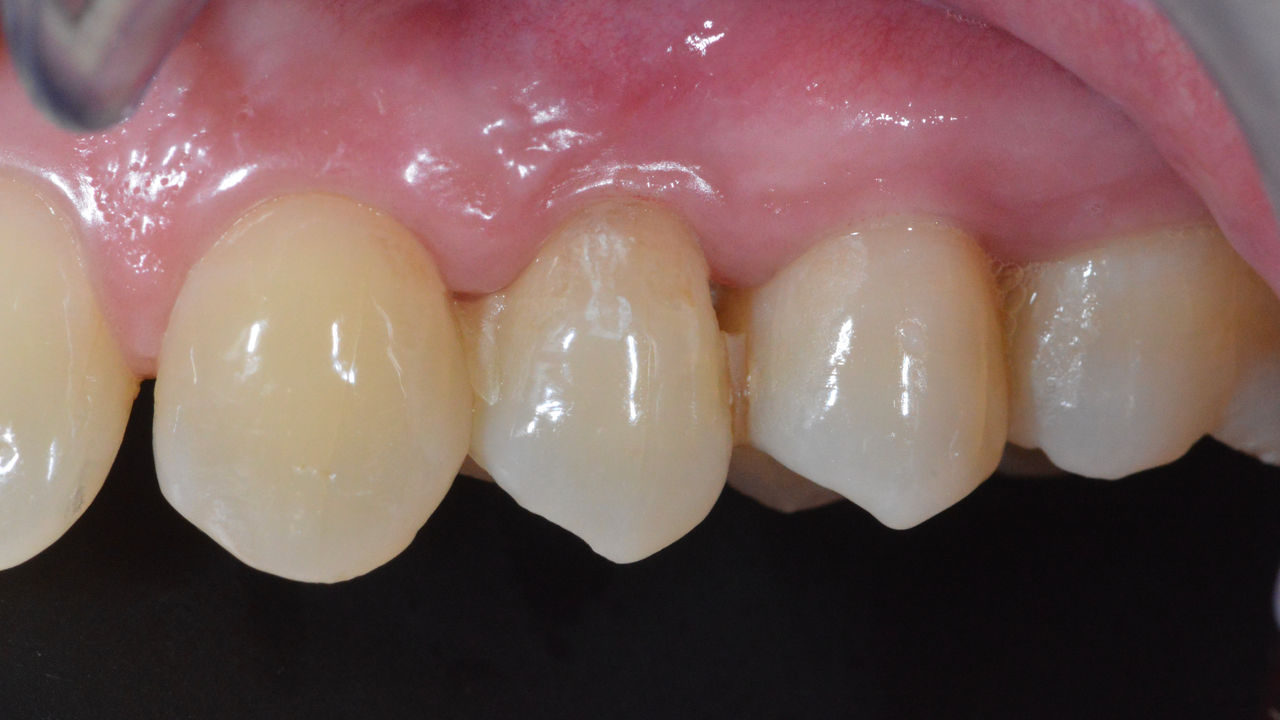

Before: Fractured ceramic restoration made from a leucite-reinforced glass-ceramic after a clinical service time of 12 years.

After: Chairside-fabricated restoration made from an advanced lithium-disilicate ceramic CEREC Tessera.